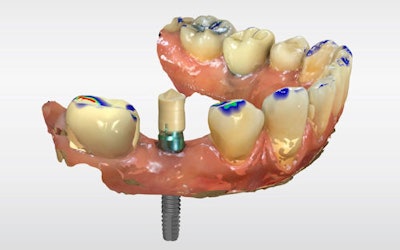

The definitive crown was then designed in CEREC software (Figure 4) using virtual articulation and occlusal analysis (Figure 5) and verified in a full-arch digital view for occlusal harmony (Figure 6). Milling was completed using CEREC Primemill with a Katana Zirconia One for Implant block, producing excellent marginal adaptation and lifelike translucency (Figure 7).

Figure 6: Full-arch digital verification.